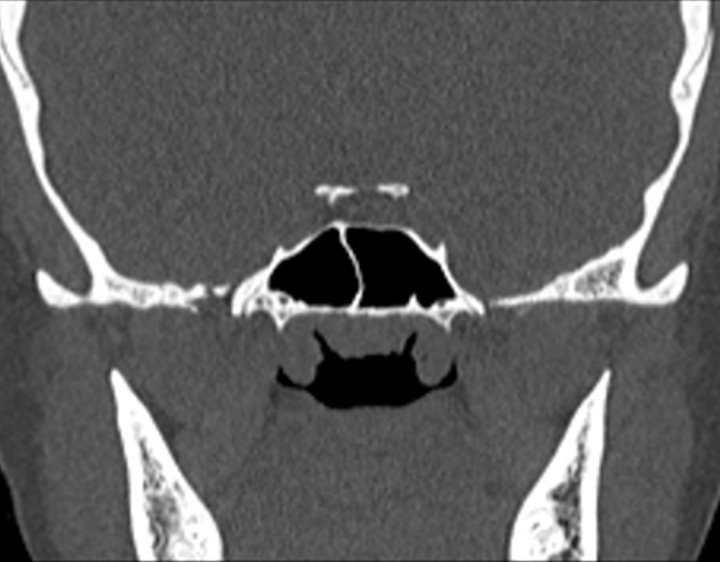

Click any image for labels.